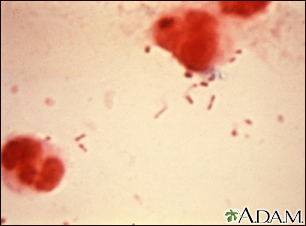

Haemophilus influenzae Type B

Haemophilus influenzae (H influenzae) type b is a bacterium that commonly caused childhood bacterial meningitis, pneumonia, blood infection, and epiglottitis (throat swelling that can block breathing). Despite its name, this bacterium is entirely different from the viruses that cause influenza (the flu). Prior to the vaccine, about 600 children died of Hib infections every year in the US. Because of routine vaccination, serious Hib disease in children is now rare.

The photo above is a Gram stain of spinal fluid from a person with meningitis. The rod-like organisms seen in the fluid are H influenzae, one of the most common causes of childhood meningitis (prior to the widespread use of the H influenzae vaccine). The large red-colored objects are cells in the spinal fluid. A vaccine to prevent infection by H influenzae type b is available as one of the routine childhood immunizations (Hib), typically given at 2, 4, and 12 months.